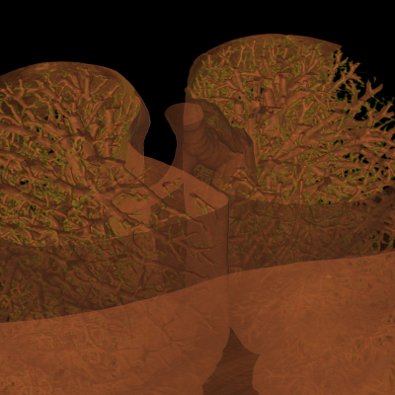

| Point Cloud | Marching Cube | Texture |

Currently four different segment visualization methods can be choosen.

The 3D segment visualization methods can be set for each individual segment. This can be done in the "view 3d" tool pane.

Experts Tip: The SegRenderer Settings allow to set much more options, e.g. the marching cube smoothing quality or the point distance.